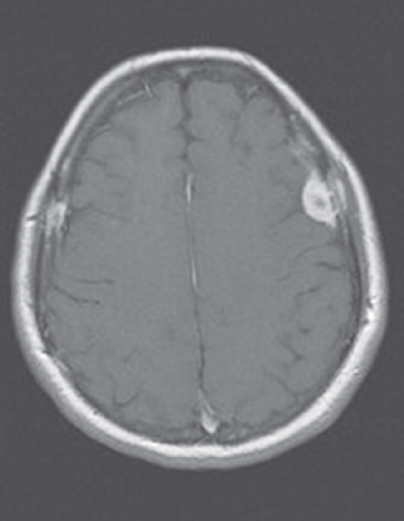

Outcome of the case. The patient in this case had already received a diagnosis of metastatic adenocarcinoma that was clearly progressive. An MRI scan of the brain revealed multiple meningeal metastases (Figure). No further investigations of his numb chin syndrome were undertaken. It was believed that the meningeal metastases were the cause of his symptoms, and he started whole brain radiation after completing the local radiation to his epidural metastasis. He may have had a mandibular metastasis, but obtaining this information would not have affected his already poor prognosis. He was referred to hospice care. ■